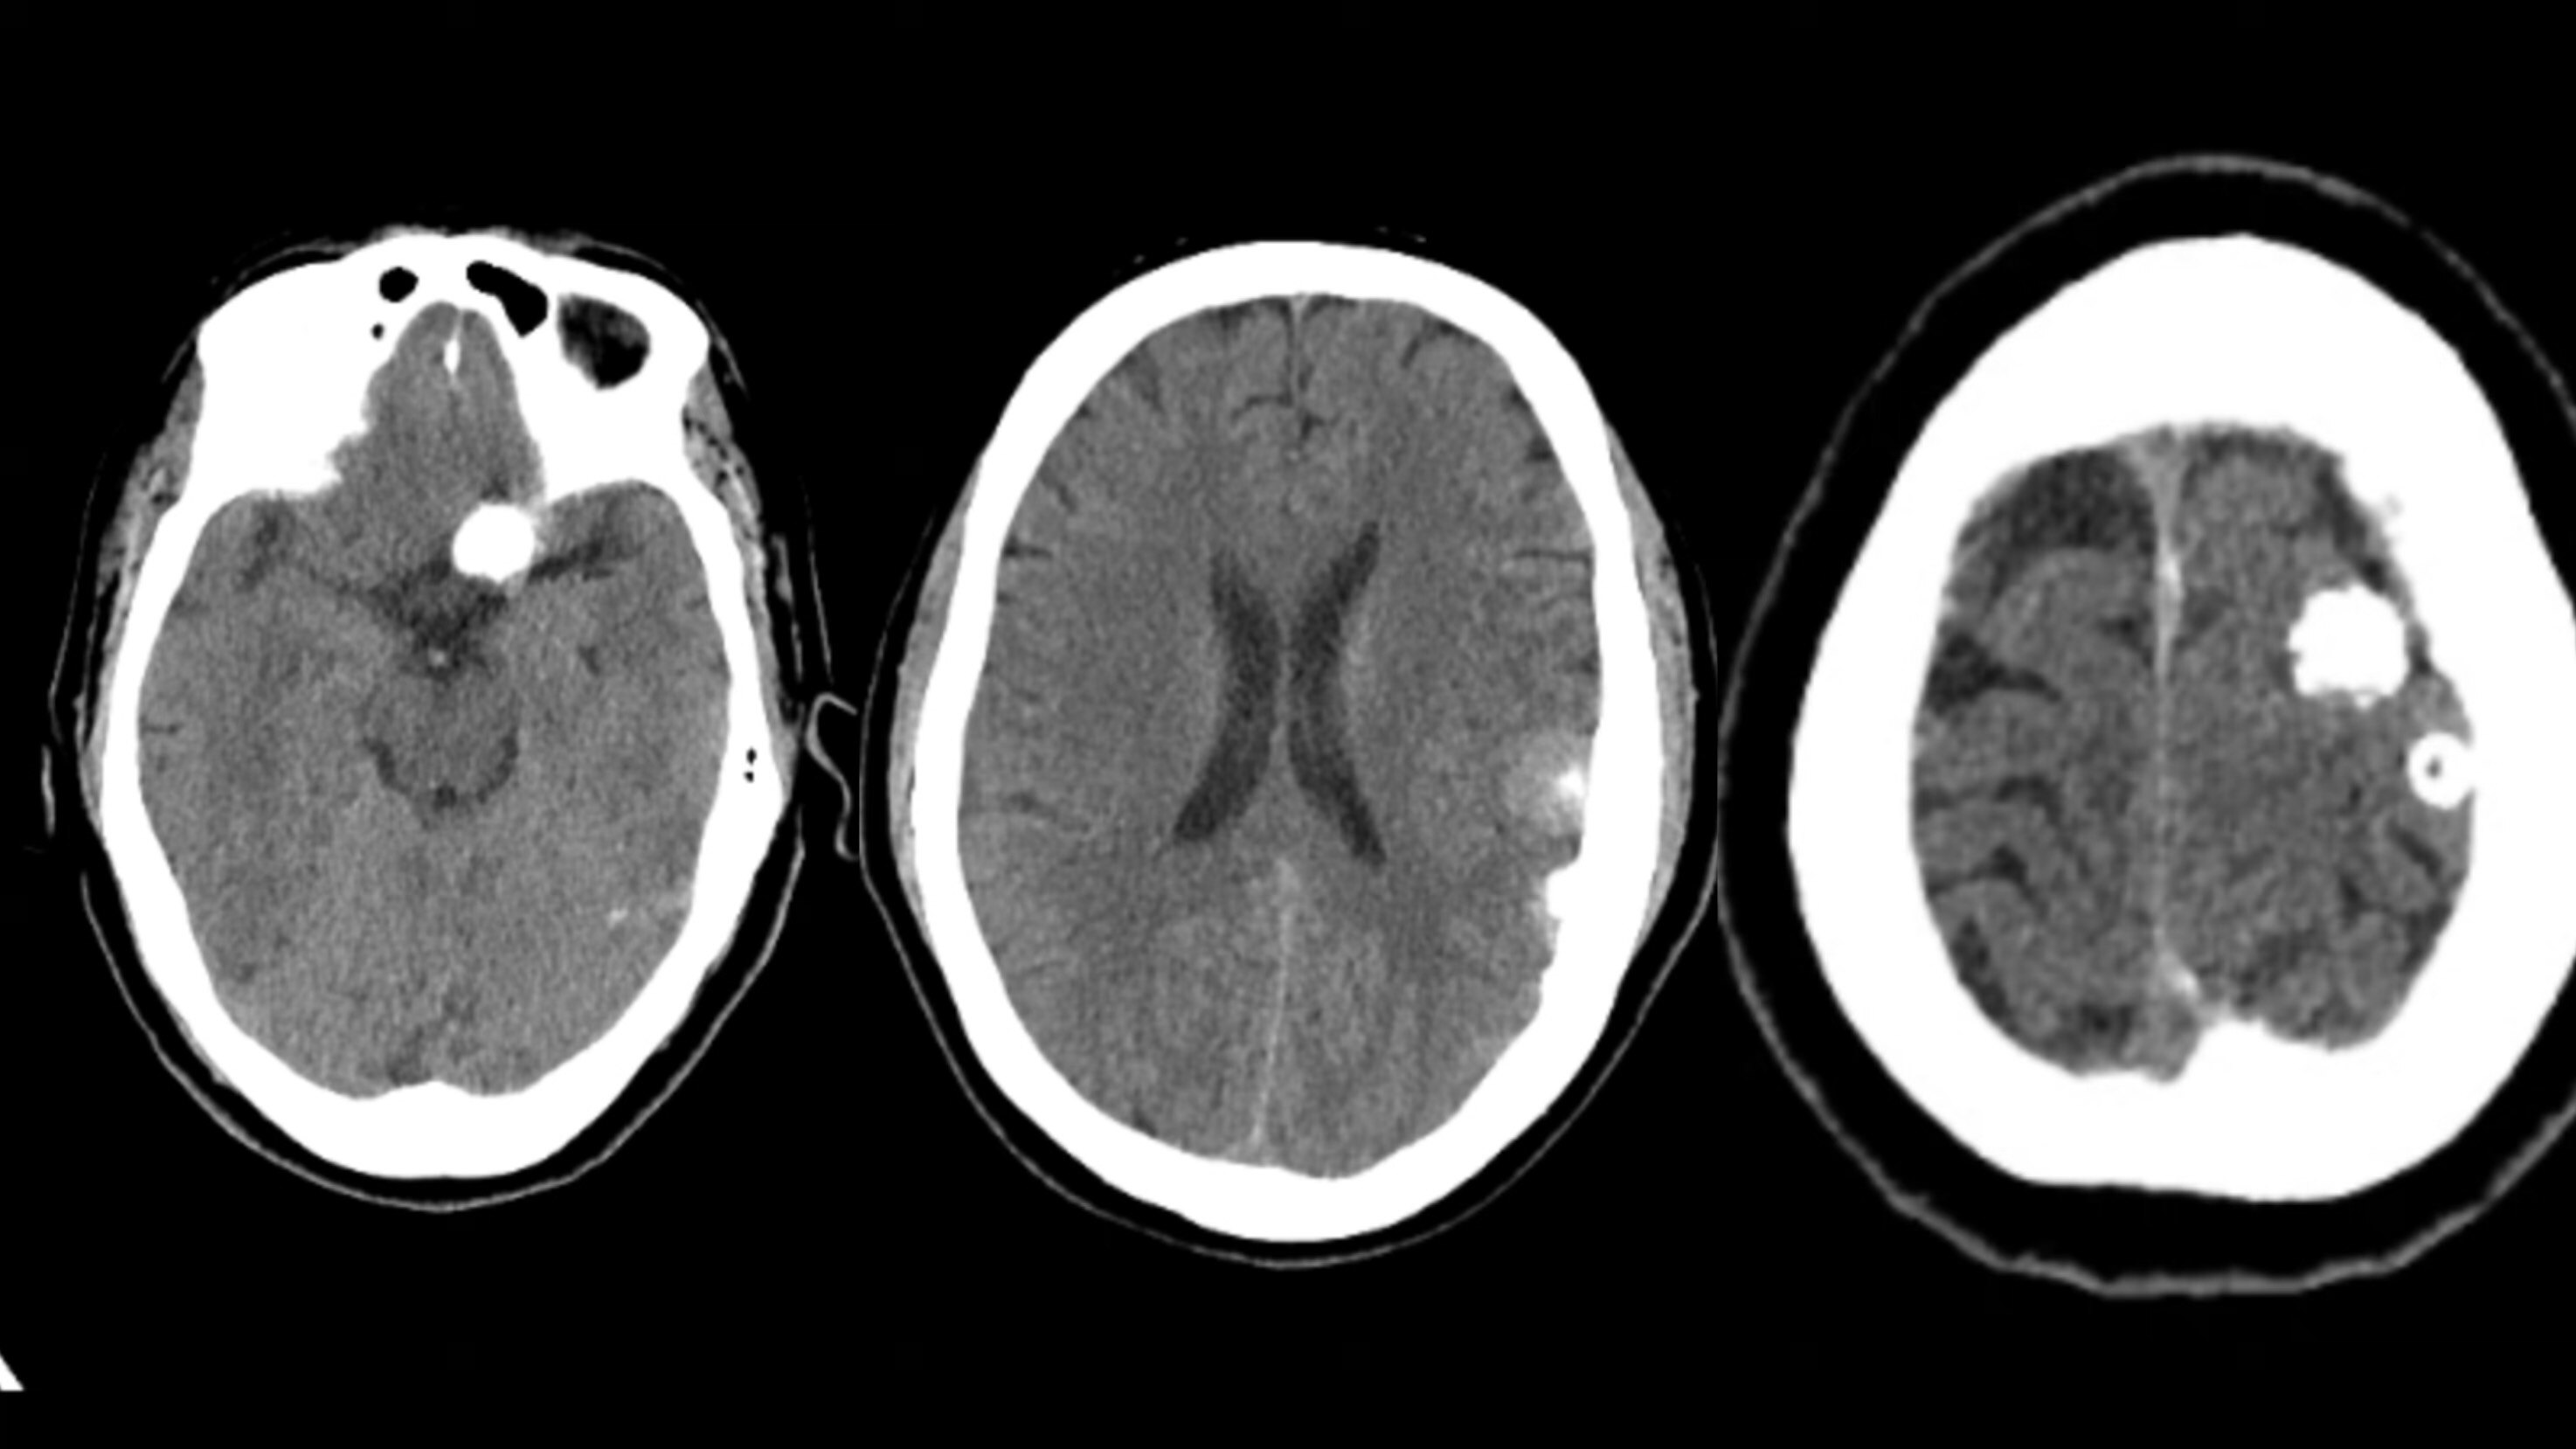

常见颅脑生理性钙化

主要见于侧脑室三角区,钙化呈圆形或不规则形,多数情况下脉络膜丛钙化